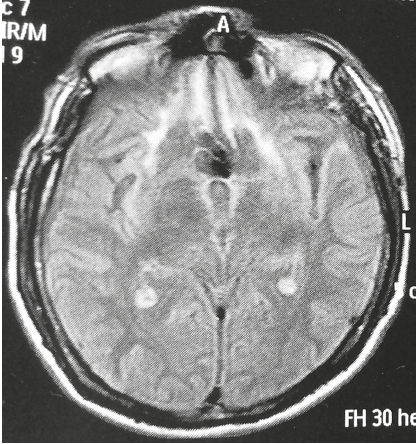

Como secuelas neurocognitivas, el paciente S. presentaba un síndrome prefrontal dorsolateral, con alteración predominantemente en la atención sostenida, la abstracción y la memoria de trabajo, y un síndrome orbitofrontal. Presentaba desinhibición conductual (p. ej., al robar objetos que llamaran su atención), jocosidad, conducta infantil y agresividad. El tipo de agresividad era el descrito en el síndrome de agresión orgánica, con explosiones de ira periódicas y súbitas, reactivas a estímulos aparentemente irrelevantes, sin planeación previa y con carácter egodistónico. Los estímulos disparadores eran de tipo interpersonal (p. ej., cuando el personal de enfermería le realizaba señalamientos con prosodia enojada). Esto podía ser suficiente para que en cuestión de segundos el paciente tuviera un episodio de agitación psicomotora con importante heteroagresión, que llegaba a comprometer su sentido de agencia y se acompañaba después de arrepentimiento. Los episodios eran más frecuentes hacia su madre, lo que generaba al paciente gran remordimiento, por lo que llegó a realizar múltiples intentos de suicidio. La resonancia cerebral mostraba extensas zonas de encefalomalacia en BA 11, 13 y 14, en la zona de transición entre OFC y VMPFC, así como gliosis en el córtex pregenual, BA 24 y25, probablemente debido al vasospasmo secundario a la rotura aneurismática en la fase aguda (figura 3).